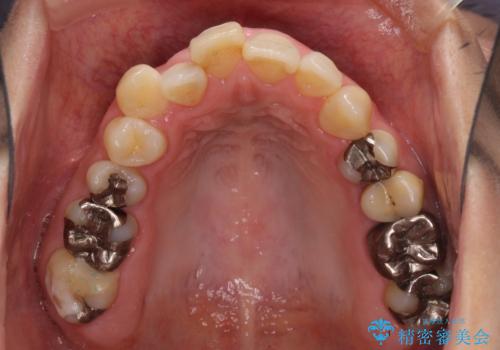

上下のバランスを取って八重歯などを解消するため、上顎左右第1小臼歯を抜歯することとしました。

根管治療の必要な歯も2本あったため、まずは根管治療を行い、ワイヤー矯正の後に補綴治療を行うこととしました。

上顎左右第1小臼歯を抜歯したことで、隙間が閉じた下顎歯列の位置まで前歯を引っ込ますことができたため、口の閉じにくさを解消することができました。